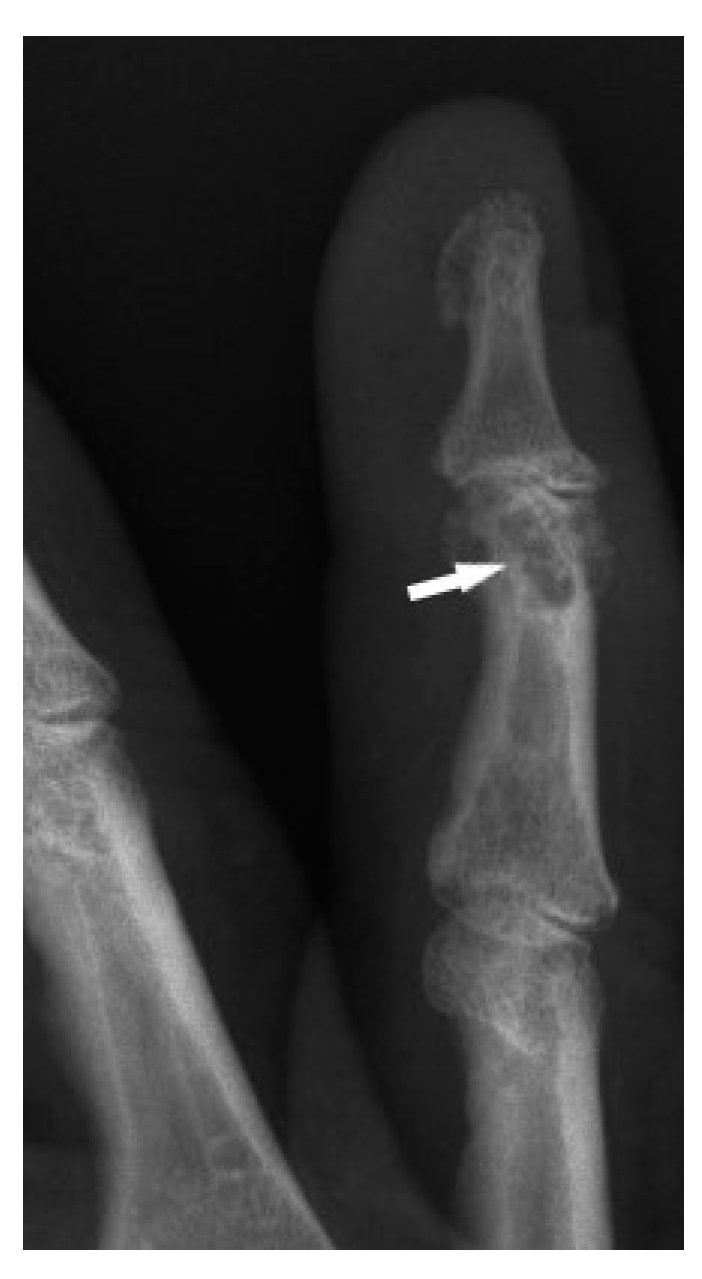

The typical cystic X-ray pattern of bone sarcoidosis was described for small bones of the hands only (Figure 1). Other skeletal sites of sarcoidosis evaluated by this modality may be a diagnostic challenge, showing no typical radiologic features of the disease. Increasingly used modern diagnostic methods such as MRI and PET-CT indicate that multifocal bone lesions are sometimes undetectable on X-ray [10,11,12].

Only the radiological pattern of the lesions in the phalanges of the hands and feet, resembling a lace on X-ray, is described as characteristic of bone sarcoidosis.

The radiographic appearance of phalanges occupied by sarcoidosis includes lytic lesions of various sizes, called cysts. Cystic lesions, mostly punched-out, may be accompanied by soft tissue nodules. The presence of large cysts increase the risk of pathological bone fracture [20] (Figure 6a,b). Numerous small cysts are more frequently observed. The articular surfaces are preserved, although cysts located in the subchondral layer might mimic erosions (Figure 7). Periosteitis is uncommon.

Features of bony destruction may be permeative and cause scalloping of the cortex, whereby cortical margins are preserved. Bone destruction with moth-eaten pattern may involve the cortex, usually with associated soft tissue swelling [19]. The cortical and trabecular architecture is usually remodeled [20]. The phalanges of the second and third fingers of the hand are most often involved, leading to the image of sausage-shaped fingers [20].

Figure 1. X-ray of the finger. Sarcoidosis. Cystic lesions in the middle phalanx head (white arrow).